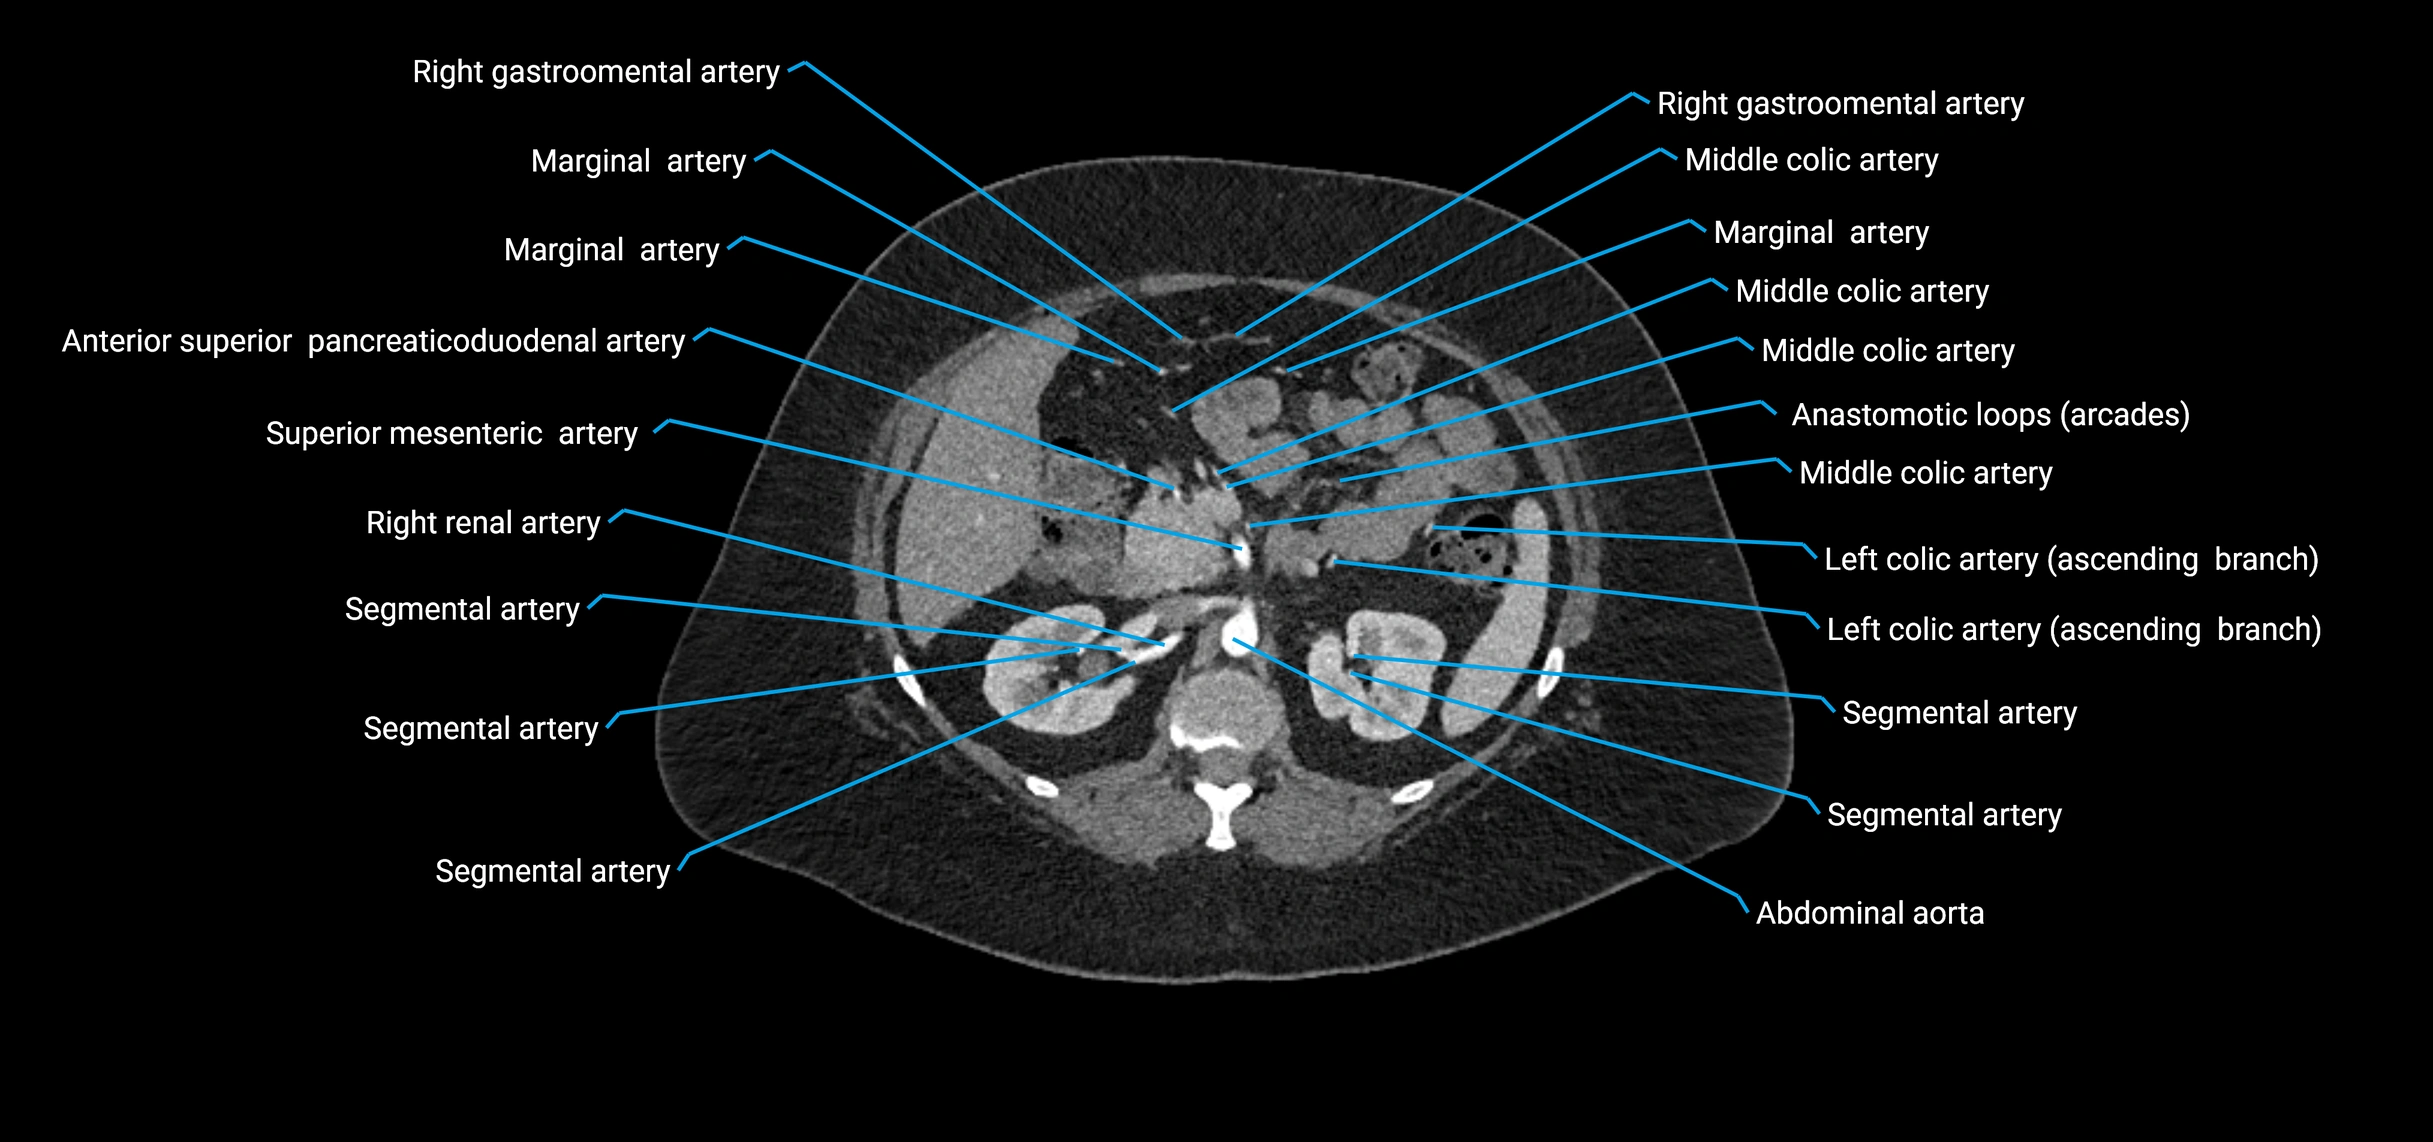

Contrast-enhanced CT (CTA):

• Gold standard for abdominal aortic imaging

• Provides excellent detail of lumen, wall, aneurysm, thrombus, and branch vessels

• Multiplanar and 3D reconstructions help in aneurysm measurement, stent graft planning, and dissection evaluation

• Detects acute rupture, traumatic injury, or occlusion with high sensitivity